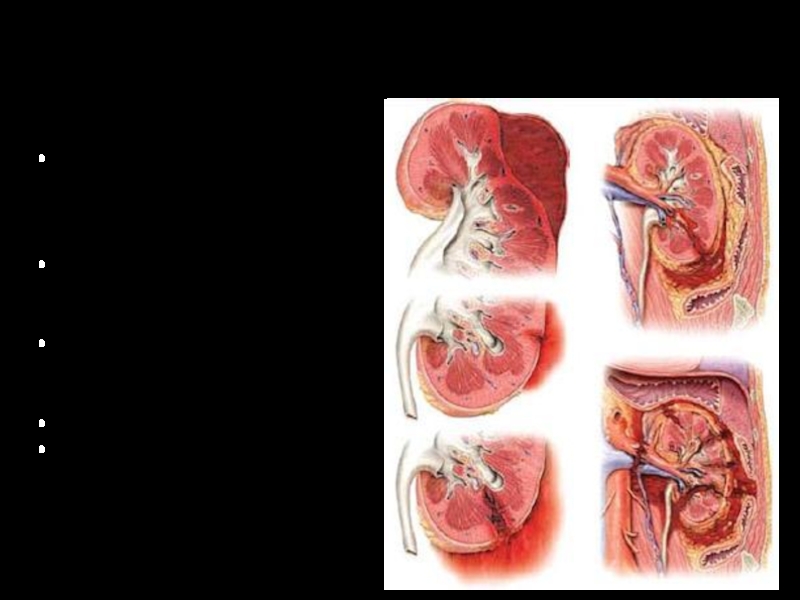

Слайд 2Закрытые повреждения почек

Повреждение жировой и фиброзной капсул с образованием гематомы

в паранефральной клетчатке

Разрывы паренхимы почки, не проникающие в почечные чашки

и лоханку

Разрывы паренхимы почки, проникающие в почечные чашки и лоханку

Размозжение почки

Отрыв почки от сосудов и мочеточника